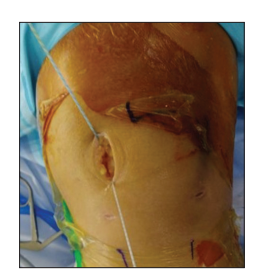

Tiếp theo, mỗi đầu chỉ được kéo ra khỏi khớp qua da bằng các vòng polydioxanone [Hình 3]. Vết mổ nhỏ tại cổng trên trong được mở rộng khoảng 2–3 cm để rút đầu chỉ ra ngoài qua lớp dưới da bằng kẹp Kelly [Hình 4].

Sau khi tất cả các đầu chỉ được định vị đúng chỗ, tiến hành buộc chỉ nội soi theo kỹ thuật “cầu chỉ” (suture bridge) để gấp mô bao khớp và phần MPFL còn lại, từ đó hoàn tất việc khâu phục hồi MPFL. Sự di chuyển của bánh chè được đánh giá cuối cùng dưới quan sát của camera [Hình 5].

Cuối cùng, vết mổ nhỏ được khâu lại bằng chỉ Vicryl 3-0 và Nylon 4-0. Các bước thực hiện chi tiết được trình bày đầy đủ [Hình 6].